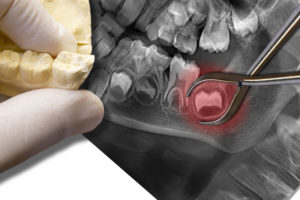

Tooth implant recovery in Thayer, MO starts with a clear plan and reasonable expectations. Recovery matters because it affects how well the implant bonds to